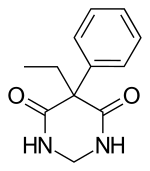

| Formula | C12H14N2O2 |

| Molar mass | 218.252 g·mol−1 |